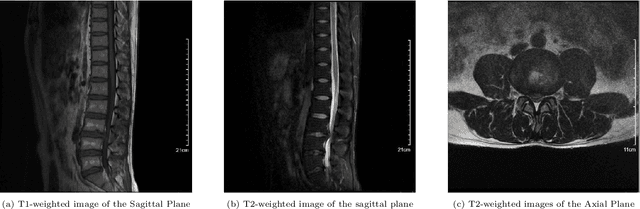

Abstract:Lumbar disc herniation (LDH) is a common musculoskeletal disease that requires magnetic resonance imaging (MRI) for effective clinical management. However, the interpretation of MRI images heavily relies on the expertise of radiologists, leading to delayed diagnosis and high costs for training physicians. Therefore, this paper proposes an innovative automated LDH classification framework. To address these key issues, the framework utilizes T1-weighted and T2-weighted MRI images from 205 people. The framework extracts clinically actionable LDH features and generates standardized diagnostic outputs by leveraging data augmentation and channel and spatial attention mechanisms. These outputs can help physicians make confident and time-effective care decisions when needed. The proposed framework achieves an area under the receiver operating characteristic curve (AUC-ROC) of 0.969 and an accuracy of 0.9486 for LDH detection. The experimental results demonstrate the performance of the proposed framework. Our framework only requires a small number of datasets for training to demonstrate high diagnostic accuracy. This is expected to be a solution to enhance the LDH detection capabilities of primary hospitals.